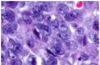

Features of Chronic Inflammation

● Lymphocytes, macrophages*, plasma cells, eosinophils